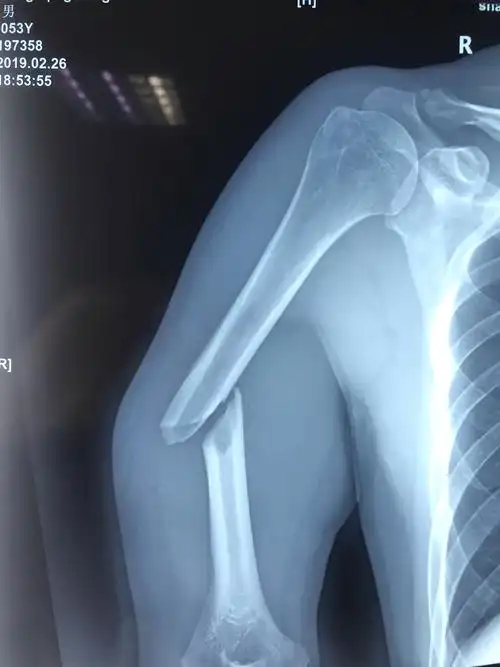

儿童肱骨病理性骨折

骨科常见疾病x线解析之肱骨远端全骨骺分离